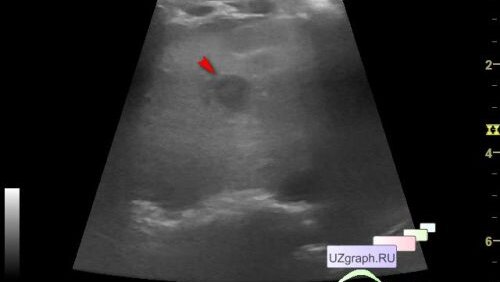

Детское УЗИ брюшной полости - Диффузно-очаговые изменения печени, толстая левая почка